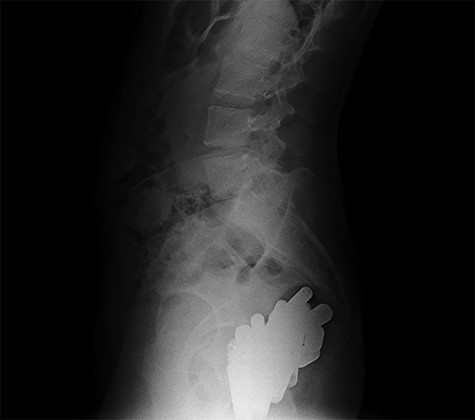

At hospitalization, the clinical examination revealed moderate pain in the lower left part of the abdomen. Laboratory analyses demonstrated moderate neutrophilic leukocytosis. Abdominal X-rays revealed the presence of many radiopaque foreign bodies on the projection of the rectum, referable to stylus batteries (Figs 1 and 2).

Erect abdominal X-rays (lateral view): confirmation of the presence of many radiopaque foreign bodies in the pelvis